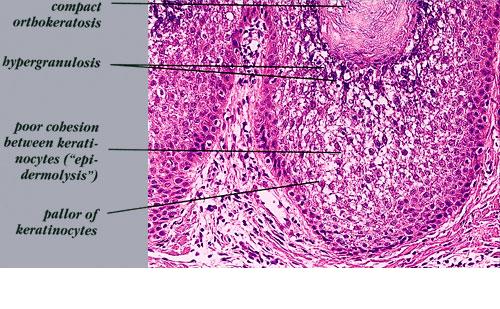

Histopathology. A characteristic histologic picture is seen in the epidermis and is referred to either as epidermolytic hyperkeratosis or as granular degeneration . It is present in bullous as well as in non bullous areas. There are variously sized clear spaces around the nuclei in the upper stratum spinosum and in the stratum granulosum. Peripheral to the clear spaces, the cells show indistinct boundaries formed by lightly staining material or by keratohyaline granules. A markedly thickened granular layer containing an increased number of irregularly shaped keratohyaline granules and compact hyperkeratosis is observed (14). When bullae form, they arise intraepidermally through separation of edematous cells from one another . The upper dermis shows a moderately severe, chronic inflammatory infiltrate. Mitotic figures are five times more numerous than in normal epidermis . Pathogenesis. Defects in keratin genes (KRT1 and KRT10) (16) are now known to be associated with this disorder. Mutations have been found in the carboxy terminal of the rod domain of keratin 1 and the aminoterminal of the rod domain of keratin 10 (17). The essential electron microscopic features are excessive production of tonofilaments and excessive and premature formation of keratohyaline granules; thus, at the periphery of the cells, numerous keratohyaline granules are embedded in thick shells of irregularly clumped tonofilaments (. The desmosomes appear normal, but the association of tonofilaments and desmosomes is disturbed, so many desmosomes are attached to only one keratinocyte instead of connecting two neighboring keratinocytes. Because of this disturbance in desmosomal attachment, blister formation takes place and real acantholysis occurs . Labeling with tritiated thymidine reveals greatly increased proliferative activity in the epidermis . It can be concluded that keratinization is both excessive and abnormal. Differential Diagnosis. Although the histologic picture of epidermolytic hyperkeratosis is diagnostic for the type of ichthyosis called epidermolytic hyperkeratosis, it is not specific for it. Hyperkeratosis is found also in several other seemingly unrelated conditions : epidermolytic keratosis palmaris et plantaris, solitary epidermolytic acanthoma, disseminated epidermolytic acanthoma, and linear epidermal nevus, usually of the systematized type. This latter entity was thought to be an entirely different condition than epidermolytic hyperkeratosis but with similar histologic findings. However, it is now known that epidermal nevi of the epidermolytic hyperkeratotic type are a mosaic genetic disorder of suprabasal keratin (l.e., point mutations of 10k alleles of epidermal cells in keratinocytes from lesional skin) that can be transmitted to offspring producing generalized epidermolytic hyperkeratosis . Epidermolytic hyperkeratosis can be an incidental finding in a variety of conditions